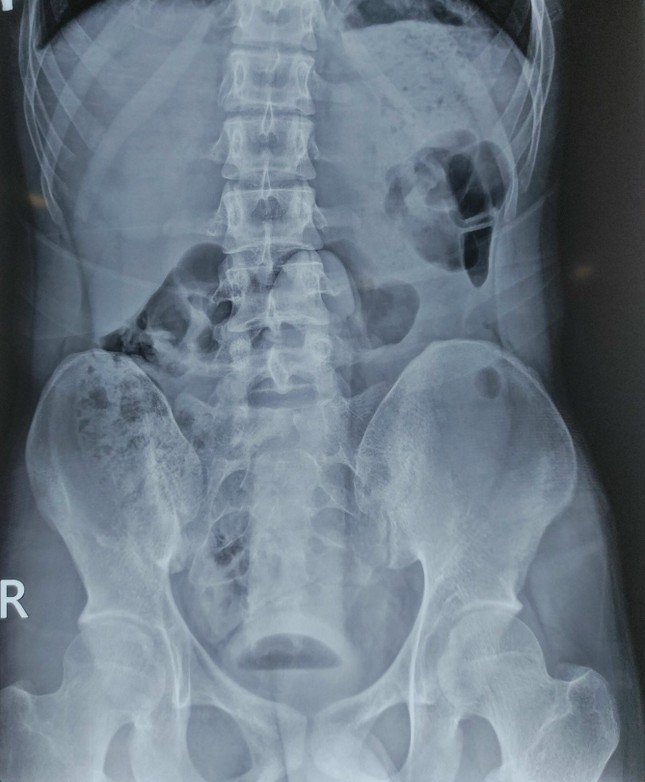

Hình ảnh X-quang cho thấy dương vật giả nằm trong đường tiêu hóa của người bệnh

Tại khoa Cấp cứu, sau khi thăm khám và chụp Xquang, các bác sĩ phát hiện trực tràng có dị vật hình dạng giống “dương vật” nằm sâu trong trực tràng nên bệnh nhân được chuyển lên khoa Phẫu thuật - gây mê hồi sức tiến hành lấy dị vật.

Do dị vật kích thước lớn nằm sâu trong trực tràng rất dễ gây tổn thương các bác sĩ đã dùng dụng cụ để lấy dị vật qua đường hậu môn một cách an toàn mà không cần phẫu thuật. Sau 30 phút, bác sĩ chuyên khoa ngoại tiêu hóa đã thành công lấy được dị vật là một dụng cụ là dương vật giả kích thước 25x5cm ra khỏi lòng trực tràng. Sau lấy dị vật tình trạng sức khỏe bệnh nhân đã ổn định.